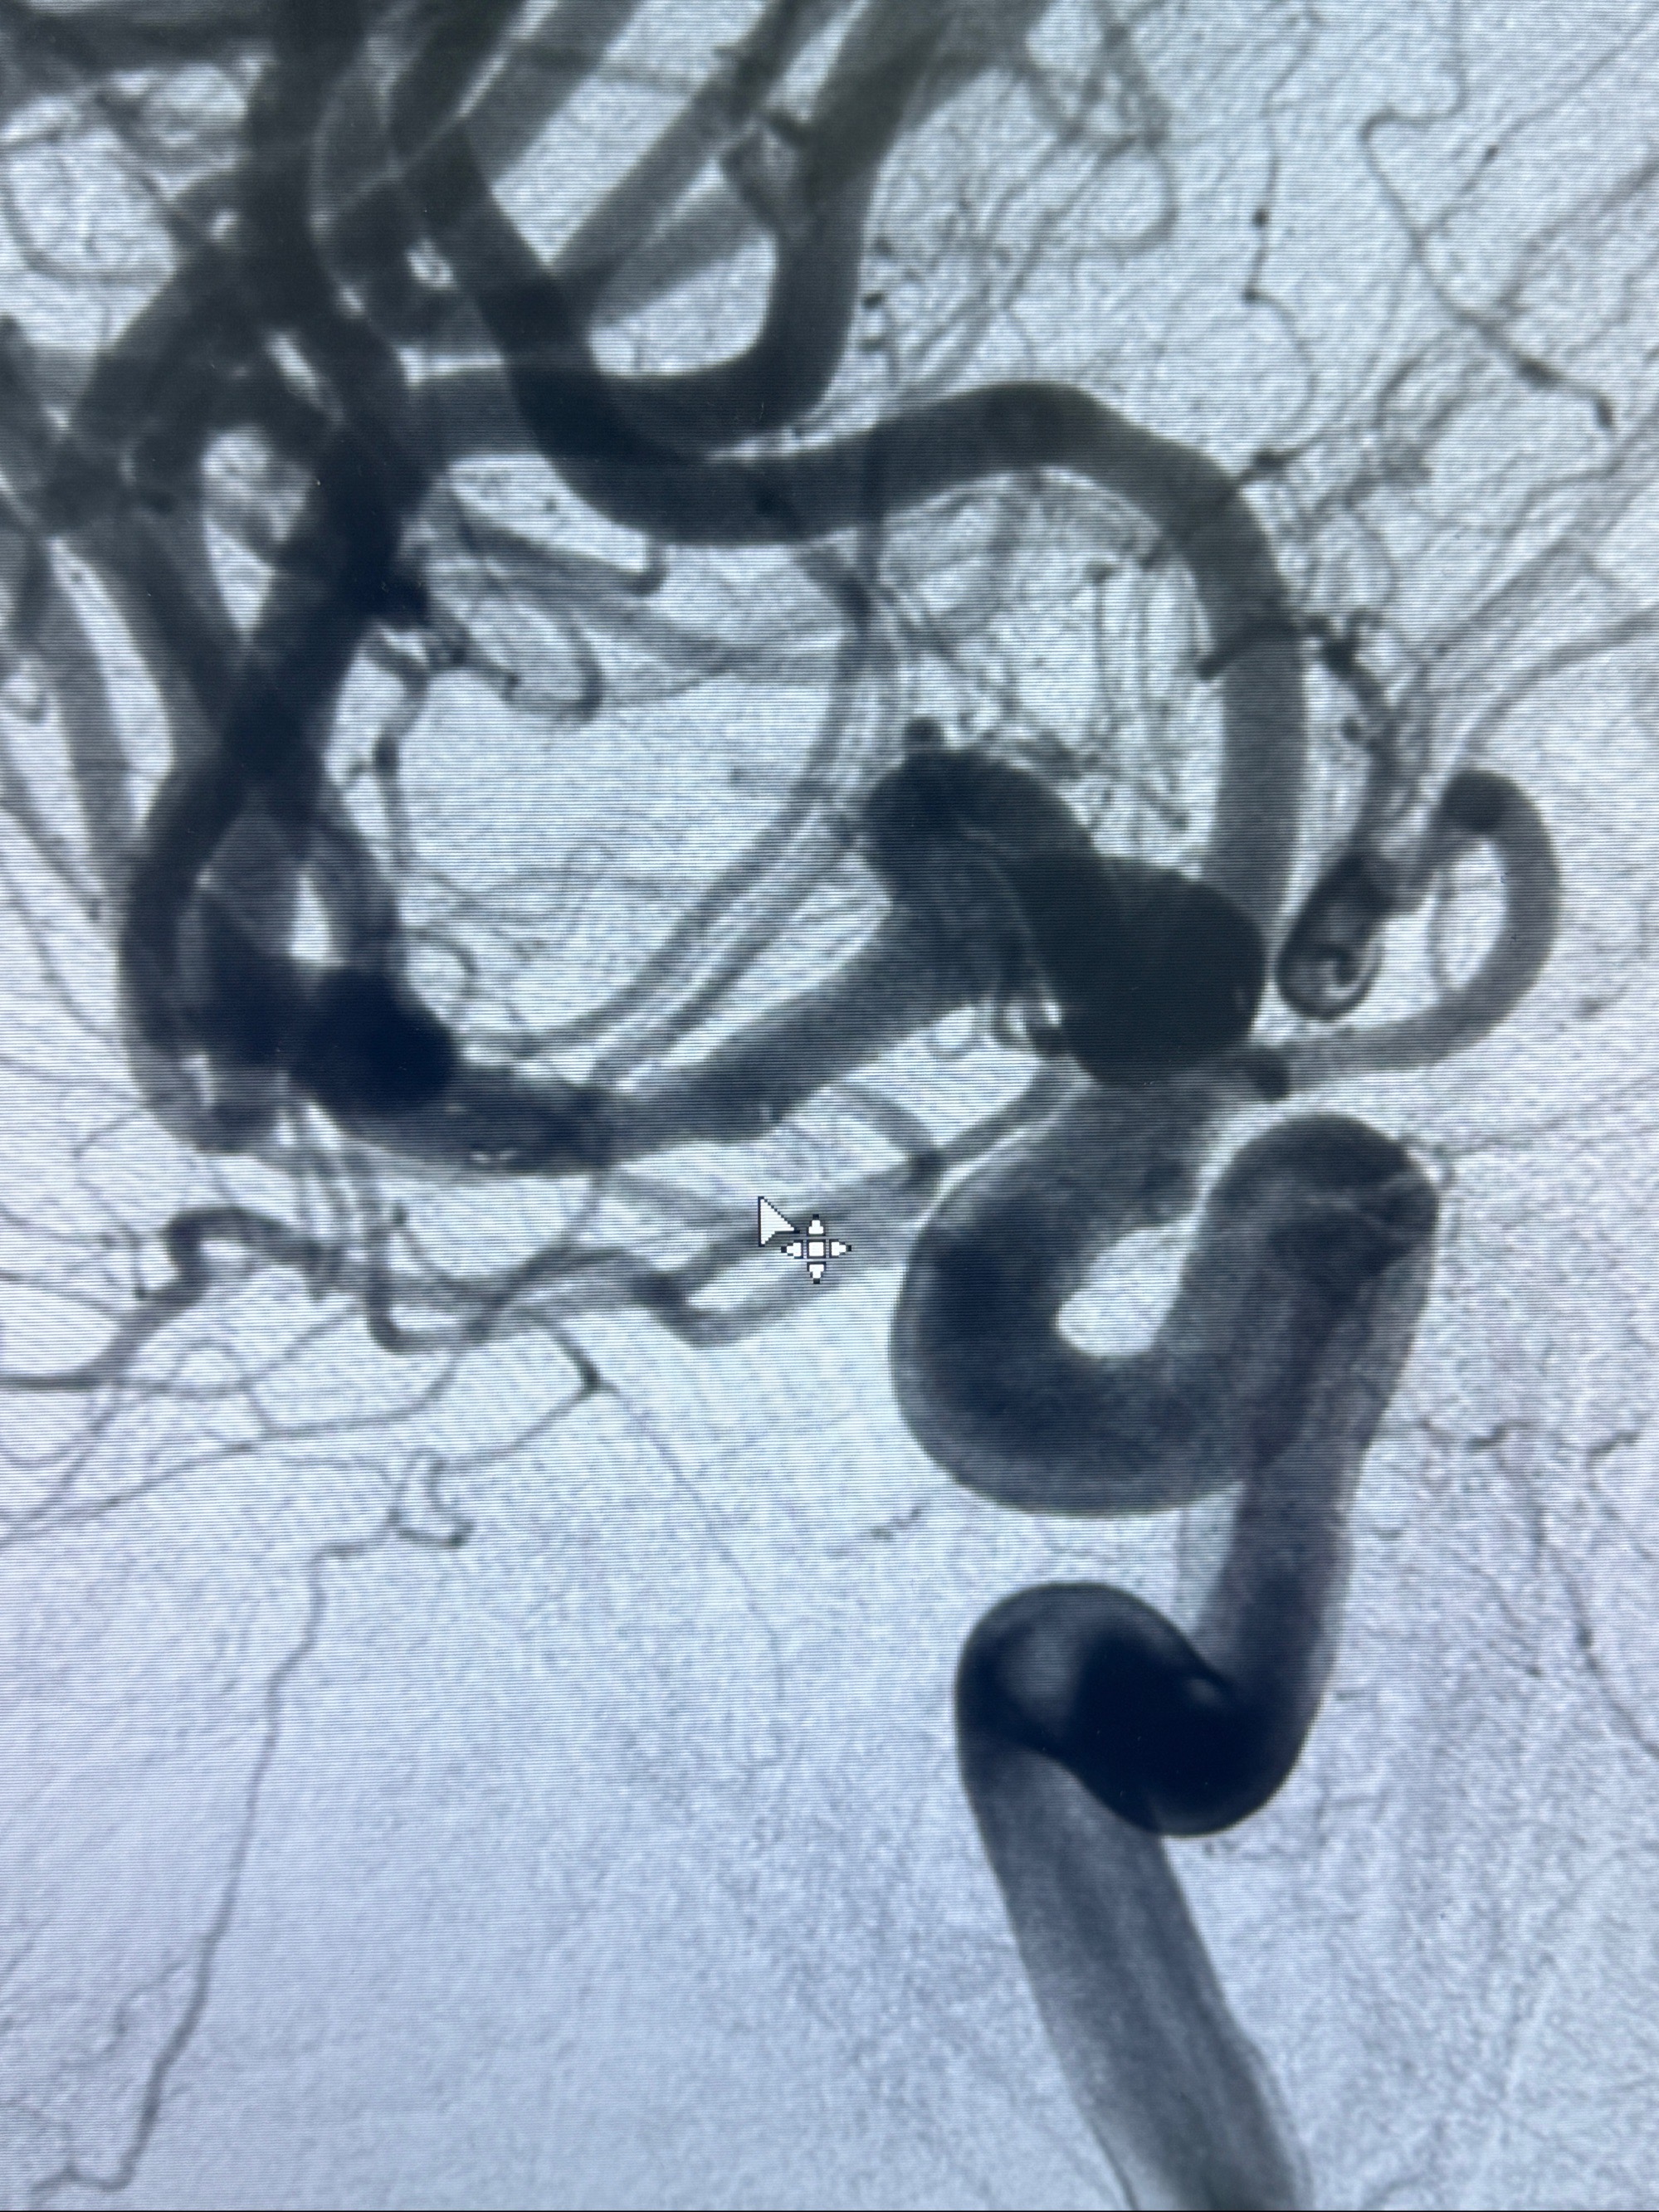

2023-11-24DSA:右侧大脑中动脉下干起始部动脉瘤,约2.3*2.5mm,形态规则

2023-12-04全麻下行支架辅助治疗

S-AB4-20mm

术后即刻CT